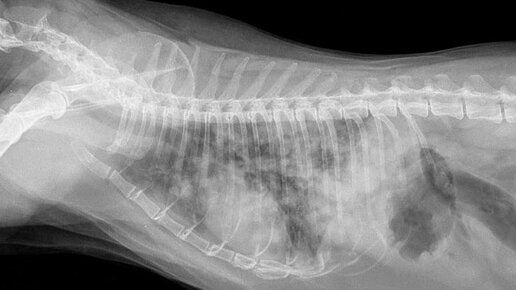

Опухоль молочной железы – довольно частая патология, по частоте встречаемости у кошек и у собак стоит на 3-4 месте среди всех патологических заболеваний. В каком возрасте чаще всего встречается опухоль молочной железы у собак и у кошек? Для собак это возраст 7-8 лет...